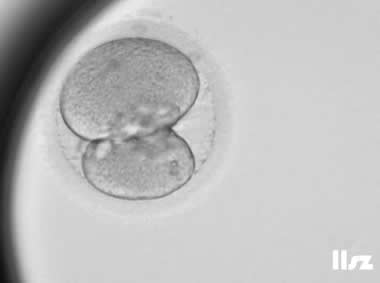

下面视频是胚胎在时差培养箱中培养至D3的整个过程,图片是D3(第68小时)的卵裂期胚胎图,本文D3胚胎评价是以D3时间点图片的形态学为依据,胚胎评级如下:

| Ⅱa级:该枚D3胚胎为8细胞,碎片在10%左右,因此评级为I级或Ⅱa级均可。 | |